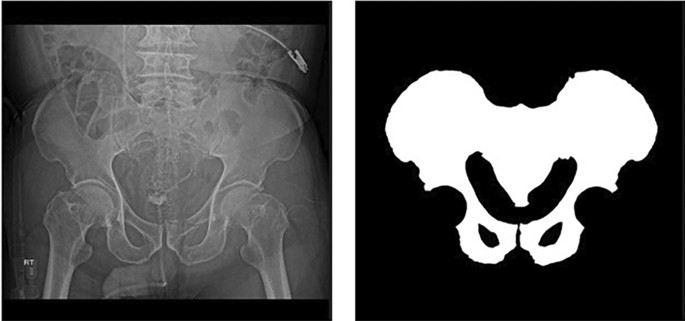

The X-ray images were collected from Gachon University Gil Hospital between January 2015 and December 2022. The dataset comprised X-ray images from 773 adults aged 18 and above diagnosed with pelvic fractures and 167 individuals without pelvic fractures. This study received approval from the Gachon University Gil Hospital Clinical Research Ethics Review Committee, and the need for informed consent was waived due to the retrospective nature of the study (GAIRB2022-153). All experimental protocols were performed in accordance with the relevant guidelines and regulations of the Declaration of Helsinki. The location of the pelvic region was determined by referencing the pelvic AP radiographic findings of radiologists and CT scans. Two trauma surgeons with more than ten years of experience confirmed all fracture sites on the pelvic AP X-ray radiographs. Subsequently, regions of interest (ROIs) were delineated along the boundaries of the pelvic ring for pelvic segmentation (Fig. 1). The ROIs in polygon form were determined using ImageJ software (version. 1.53t, National Institutes of Health, Bethesda, MD, USA).

Pelvic ring segmentation.